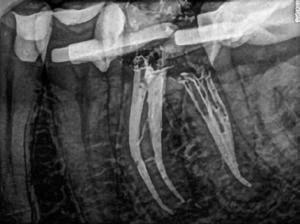

A páciens a jobb alsó első nagyőrlőfogából kiinduló közepes erősségű fájdalom miatt kereste fel a rendelőnket. Periapikális röntgen és CBCT-felvétel is készült. Mindkét felvétel a mesiobukkális gyökércsúcs körül található radiolucens elváltozás jelenlétét igazolta. Ezenfelül a mesialis gyökérben két betört eszközdarab is észlelhető volt. Az egyik a középső gyökéri harmadban a gyökérgörbület előtt volt megtalálható, a másik pedig kicsivel a gyökérgörbület után (12–13. ábra).

12. ábra: A kiindulási CBCT-felvételen jól látható a periapikális felritkulás. – 13. ábra: A kiindulási röntgenfelvételen látható a két betört eszközdarab.